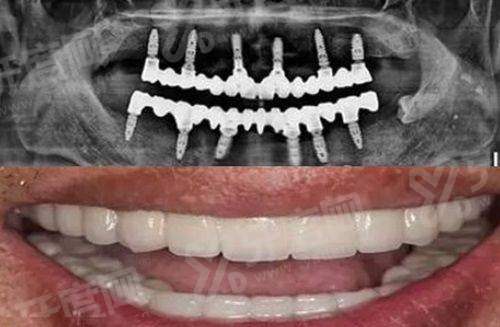

1、上海中喜优牙口腔医院种植牙价格表:

上海中喜优牙口腔韩国登腾种植牙价格:1380元起一颗

上海中喜优牙口腔瑞士iti种植牙价格:4980元起一颗

上海中喜优牙口腔瑞典诺贝尔PCC种植牙价格:6500元起一颗

上海中喜优牙口腔半口即刻种植牙价格:2万元起

上海中喜优牙口腔全口微创种植牙价格:3万元起